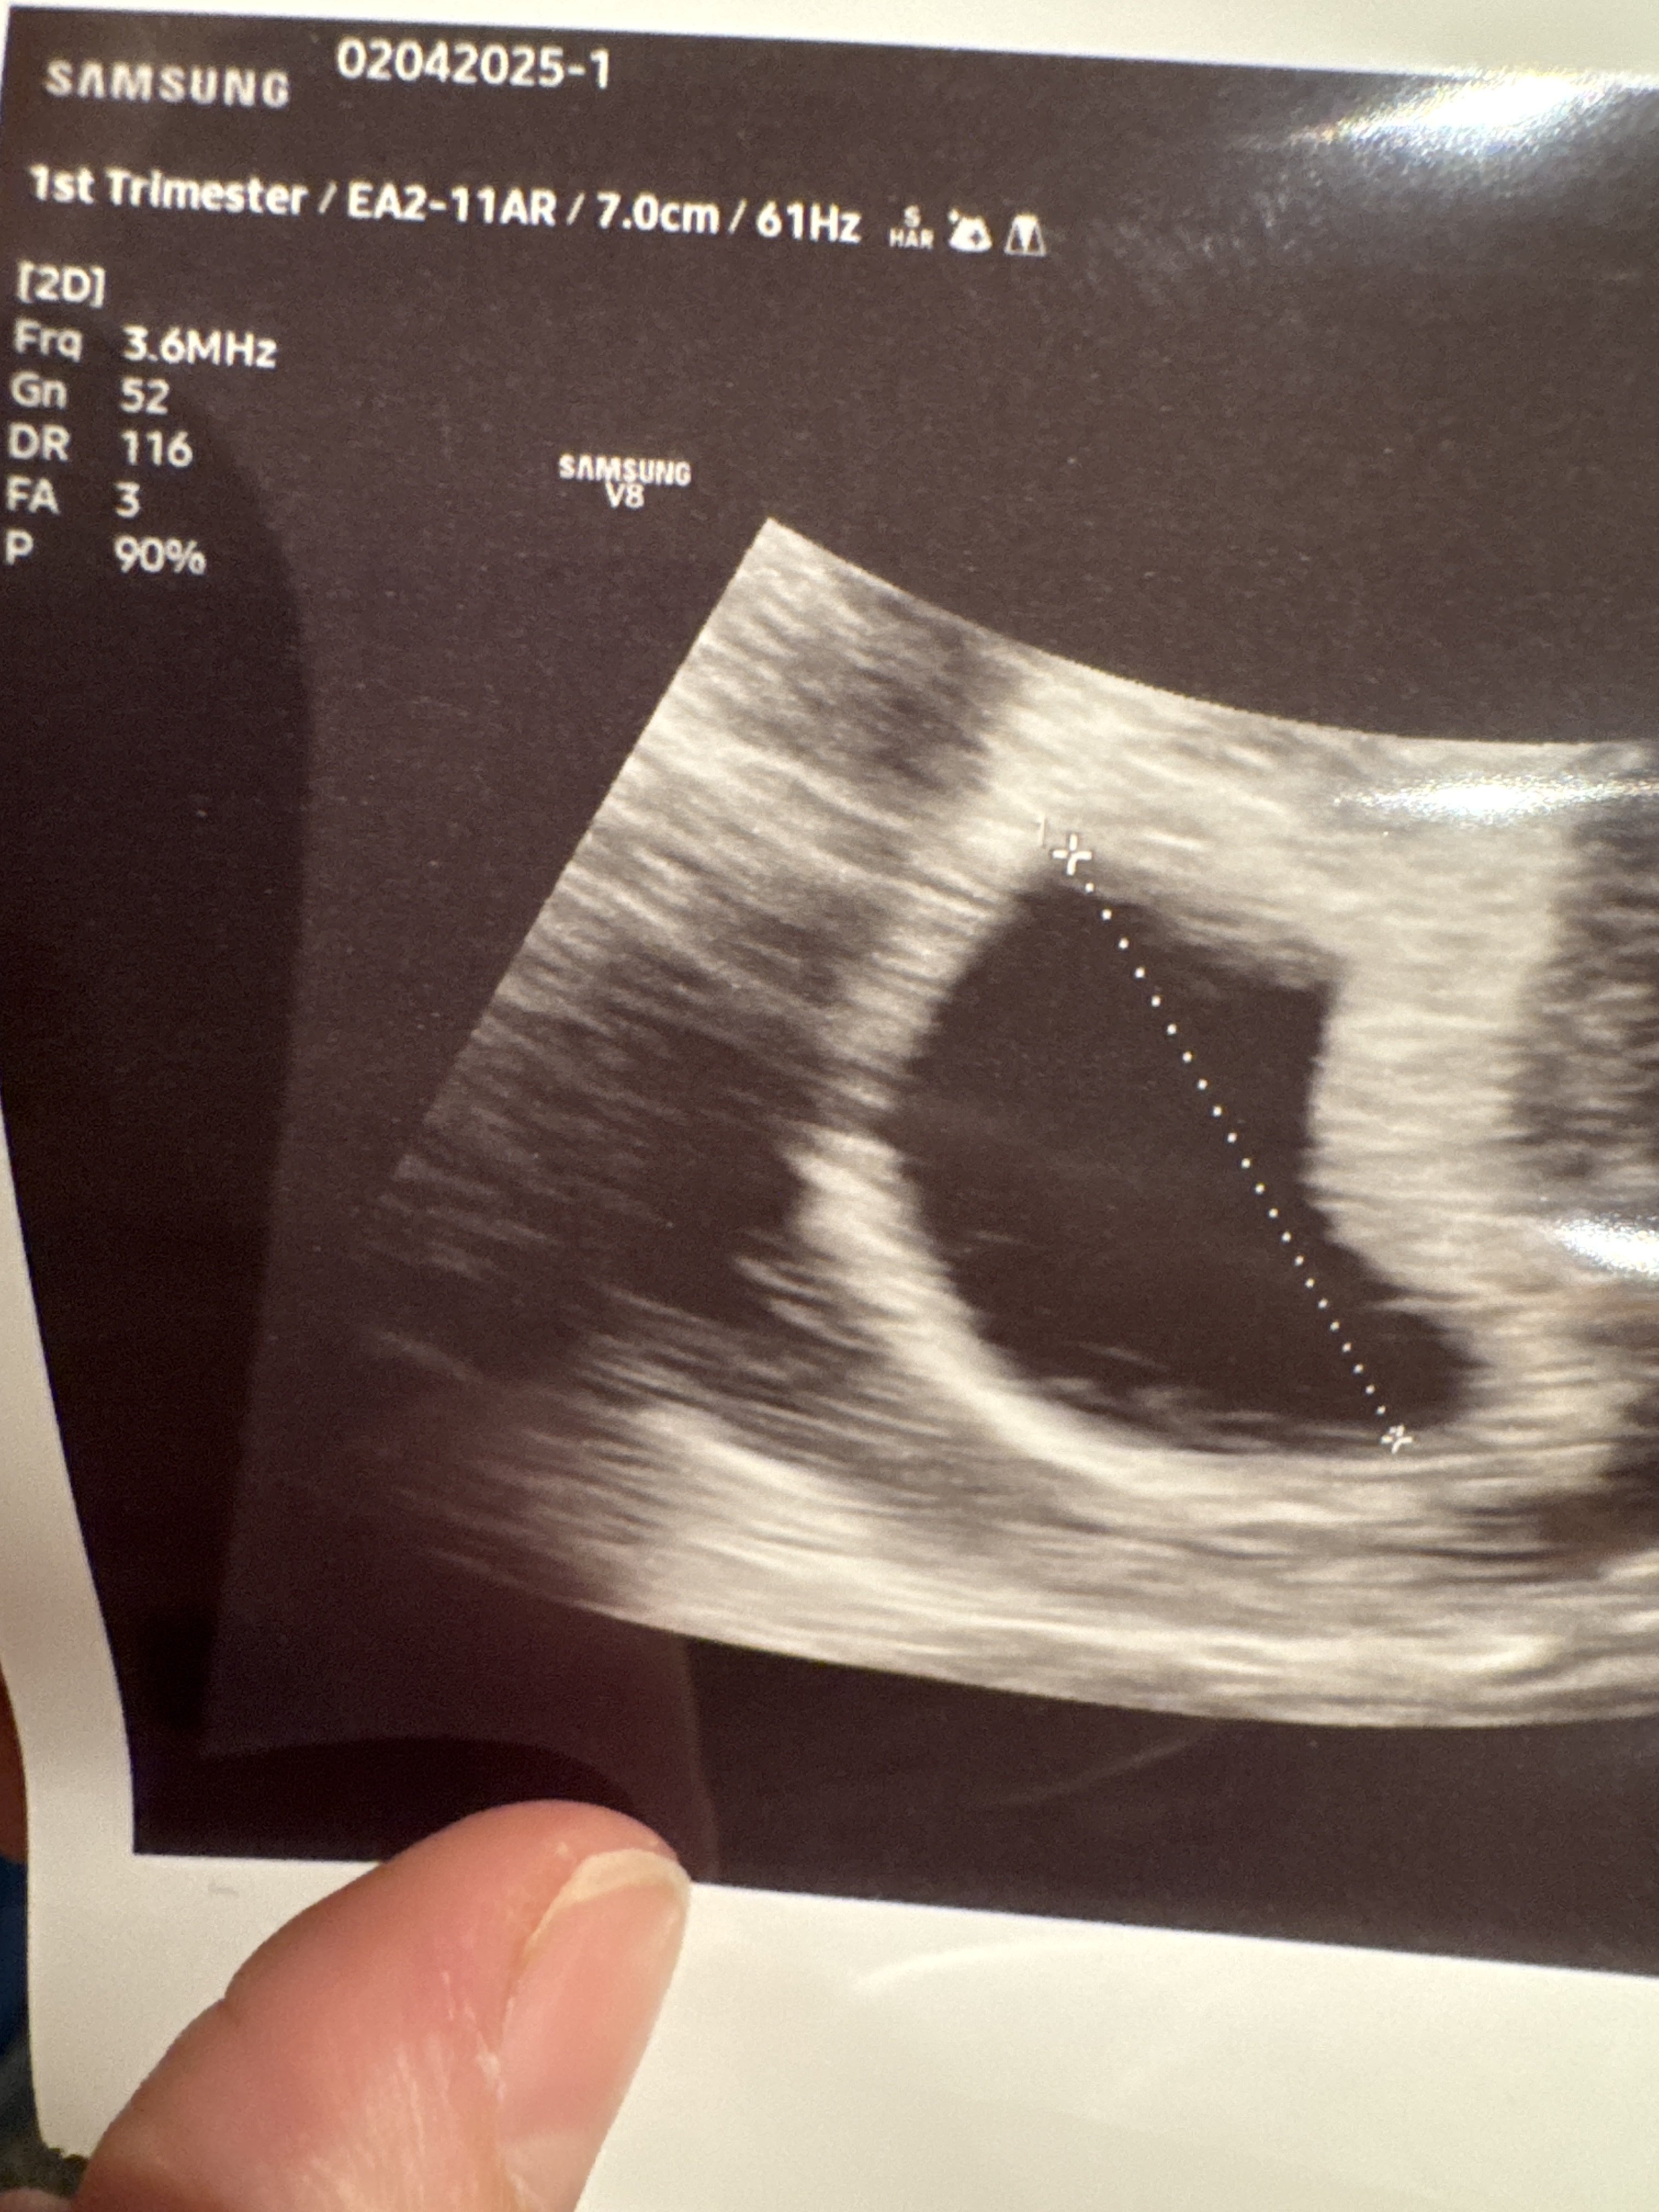

Byłam dziś na badaniach - tydzień ciąży z miesiączki i z USG zgadza mi się co do dnia 🙂 serca nie było jeszcze, ale tego się spodziewałam. Poszłam po chorobowe i dostałam, także mogę już spać ile mi się podoba. Dziś opaska mi pokazuje 13 godzin snu w ciągu doby, a wcale się jakaś wypoczęta nie czuję 🤦‍♀️

Ja dzisiaj też dostałam się do lekarza ale prócz jaja nie ma nic więcej a już powinno być.. także chyba tym razem się nie udało :( mam jeszcze czekać tydzień i zobaczymy ale nie wierzę w cuda :( no cóż nie tym to innym razem

7+0

Mam czekać jeszcze tydzień